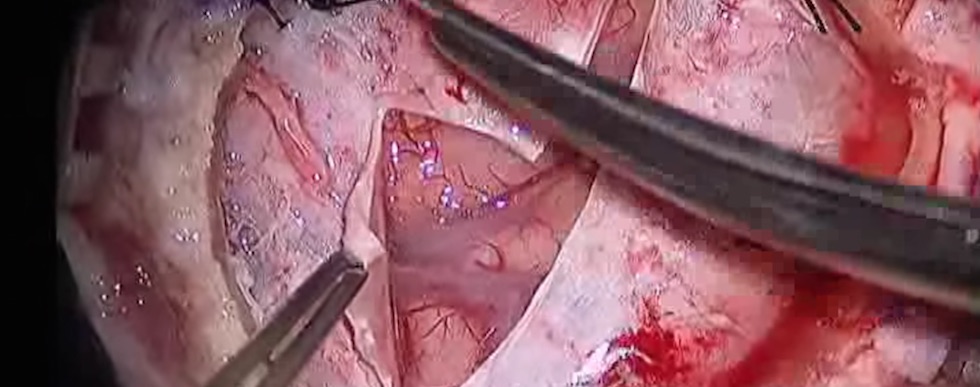

Вашему вниманию предлагаются видеозаписи лекций выдающихся врачей и преподавателей, выступления на конференциях, съемки хирургических операций, полезные советы по сохранению здоровья, красоты и профилактике заболеваний, переводы зарубежных медицинских видеоматериалов, медицинские статьи и блоги врачей. Вам также могут быть интересы отзывы о лекарствах.